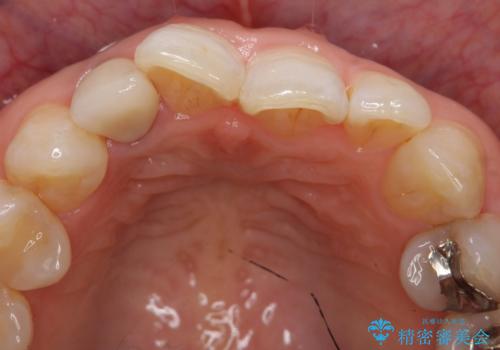

- 右上2番目の歯の変色が気になるといらっしゃった方の症例です。

再根管治療終了後、オールセラミッククラウンによる補綴を行いました。

今回用いたオールセラミッククラウンはジルコニアフレームという白い素材の上にセラミックを盛っているため、審美性が非常に高いのが特徴です。